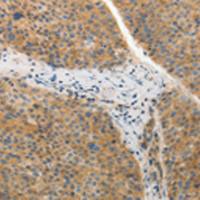

| Applications: | WB,IHC,IF,FC |

| IHCpositivecontrol: | adenocarcinomaofhumanendometriumtissue |